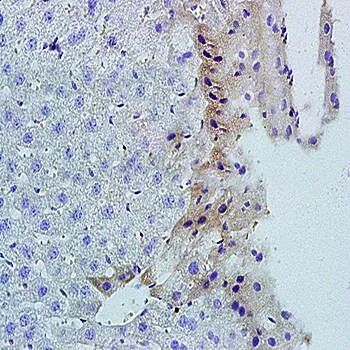

Immunohistochemical analysis of formalin-fixed and paraffin embedded rat spleen tissue (dilution at:1:200) using TNFSF14 antibody